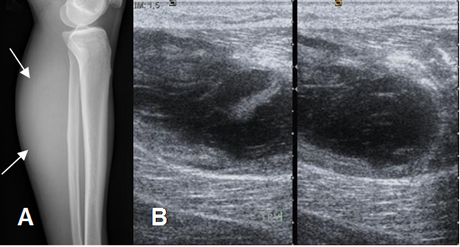

Fig 10. Hematoma muscular.

A: Rx lateral. Prominencia en los tejidos blandos de la región posterior.

B: Ecografía axial. Colección líquida y heterogénea dentro del músculo gemelo, por hematoma.